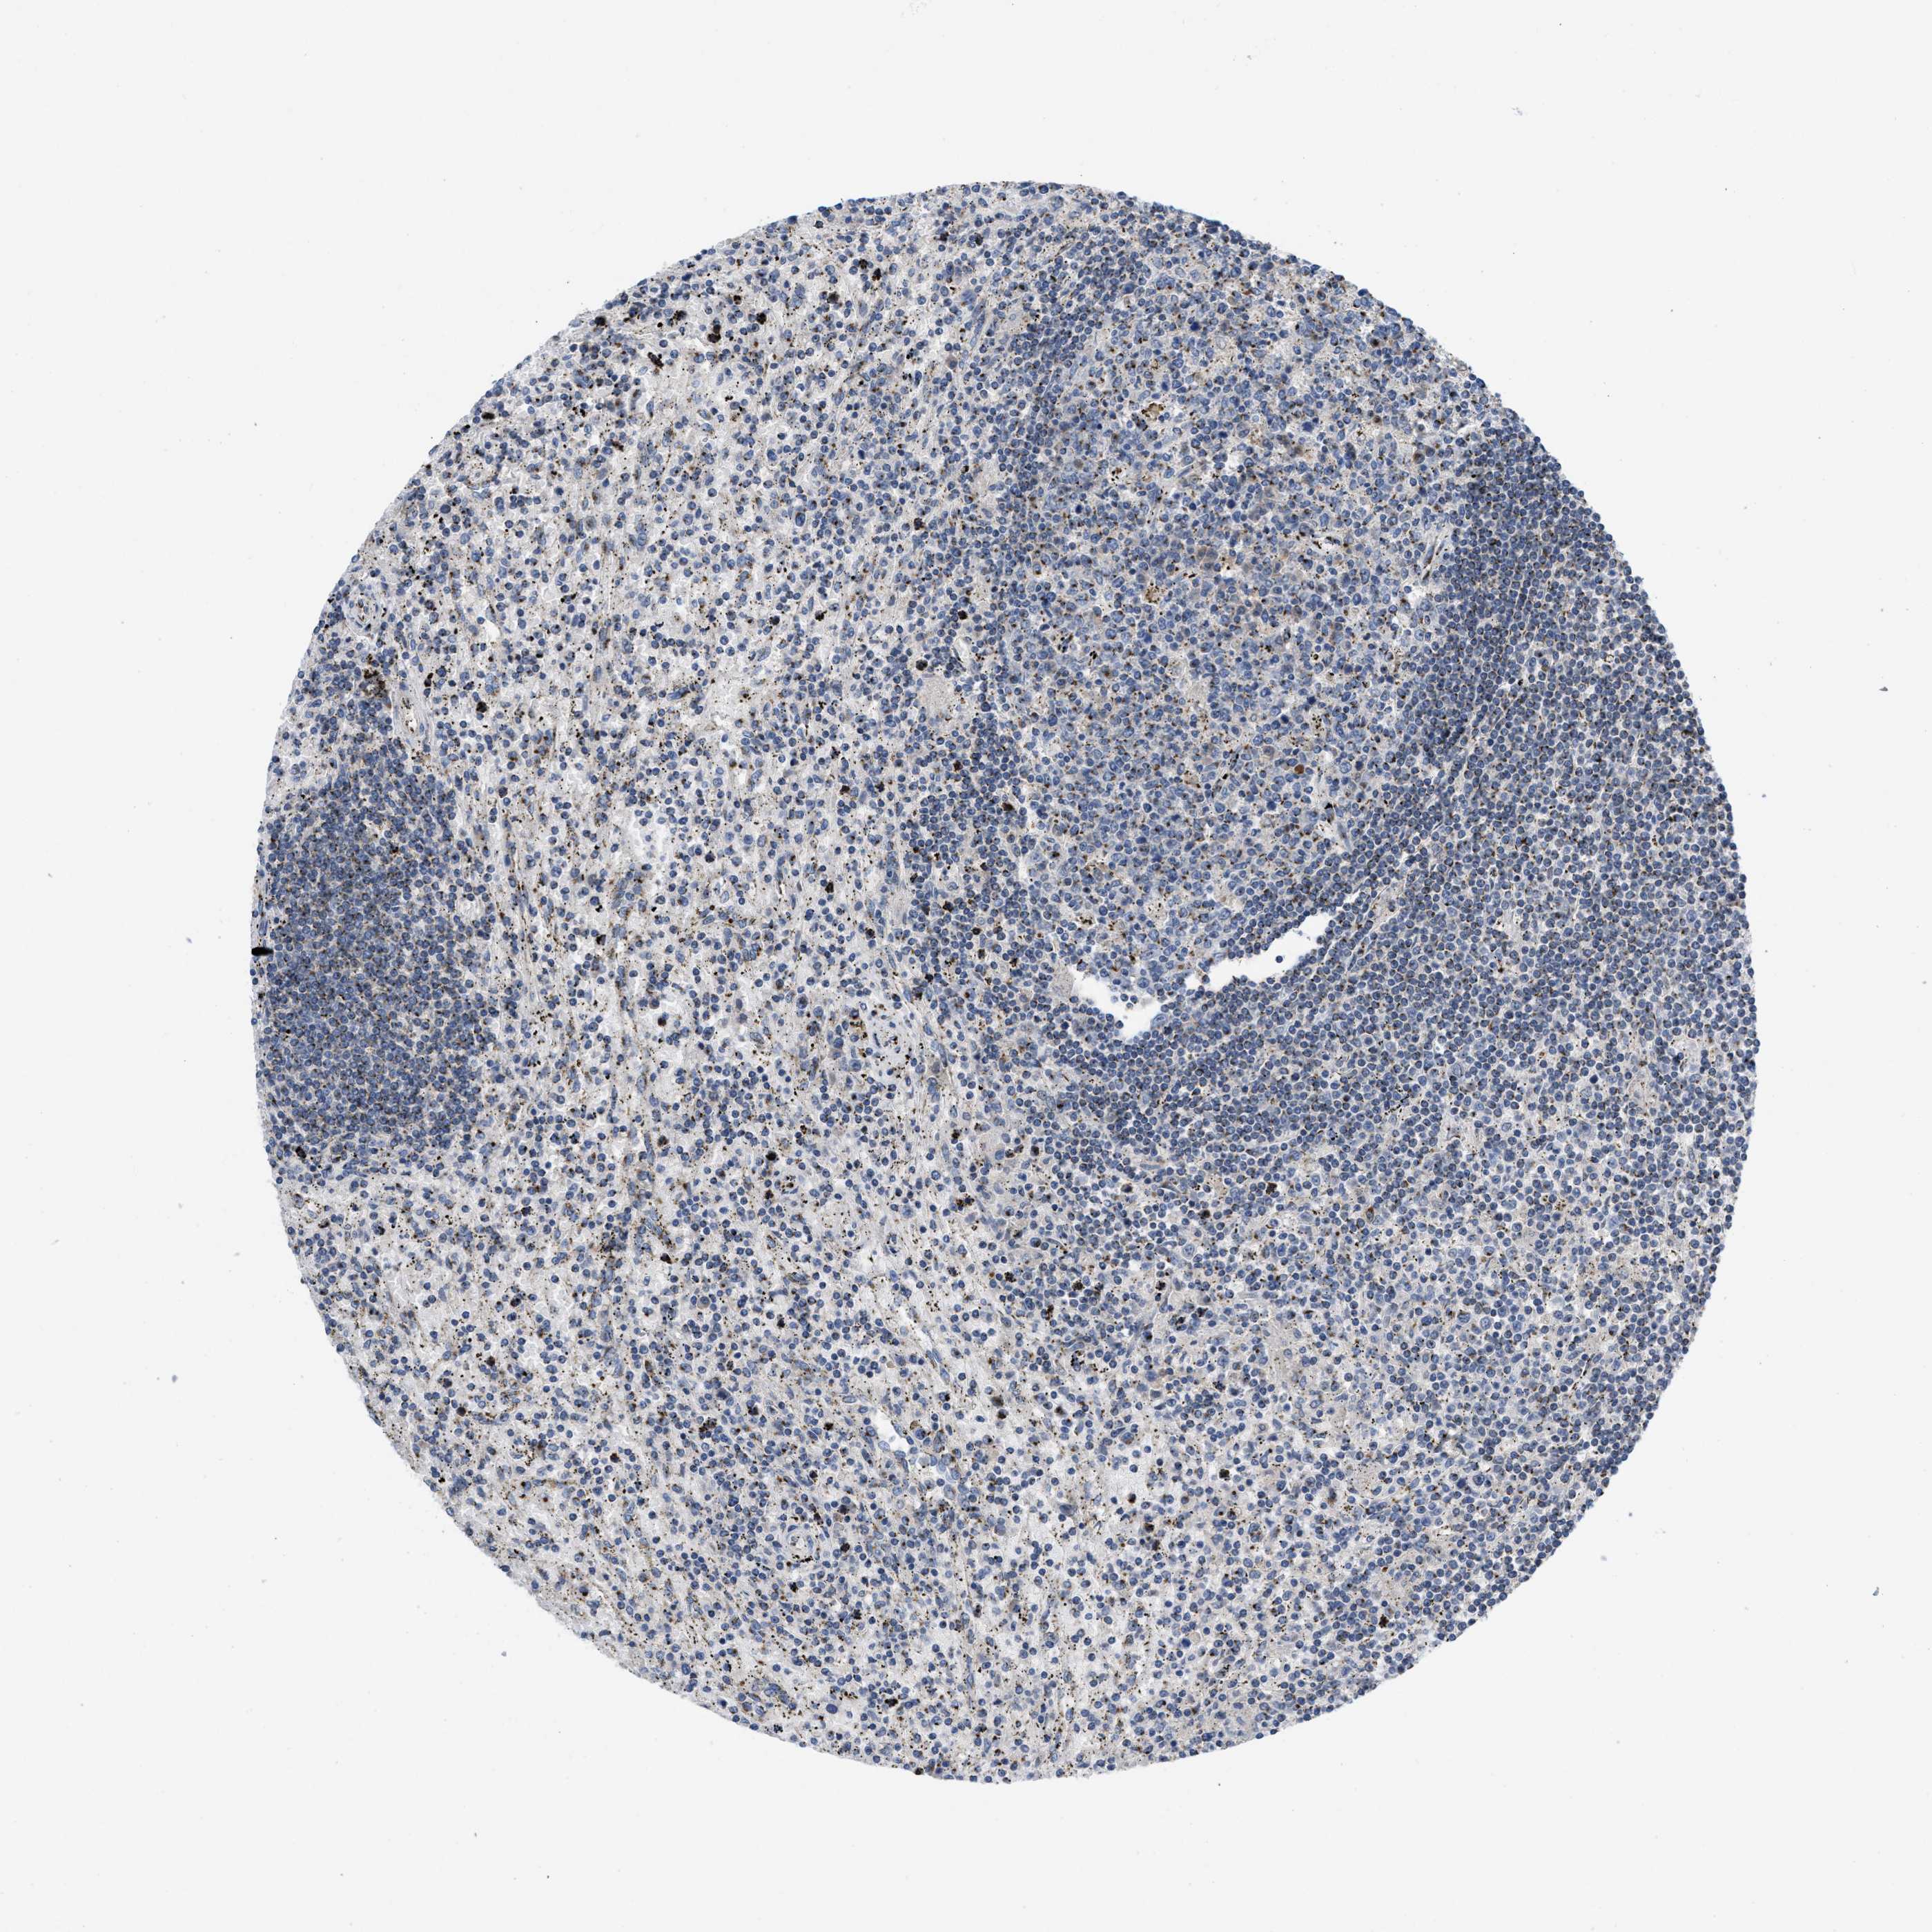

CANCER LYMPHOMA Show tissue menu

LYMPHOMA - Protein expressioni

A mouse-over function shows sample information and annotation data. Click on an image to view it in a full screen mode. Samples can be filtered based on level of antibody staining by selecting one or several of the following categories: high, medium, low and not detected. The assay and annotation is described here.

Each image is clickable and will lead to virtual microscopy that enables deeper exploration of all samples and also displays staining intensity scores, fraction scores and subcellular localization as well as patient and tissue information for each sample.

Antibody HPA018821

Hodgkin's disease, NOS

Malignant lymphoma, non-Hodgkin's type, High grade

Malignant lymphoma, non-Hodgkin's type, Low grade